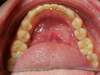

Le potentiel de croissance de la mandibule ne peut pas s'exprimer et la croissance de celle-ci "s'enroule sur elle-même". Si l'enfant n'est pas traité, le décalage des mâchoires dans le sens antéropostérieur de classe II va s'aggraver et avec pour signes esthétiques un profil convexe avec un menton en retrait dans le profil, une lèvre inférieure en retrait et éversée aussi et une occlusion dentaire de classe II. Certains patients auront aussi des morsures palatines. Ceci pourra bien sur se corriger avec un appareillage multi-attaches bi maxillaires et le port d'élastiques de classe II ou la pose d'un Forsus à un âge où l'enfant doit déjà gérer sa puberté...